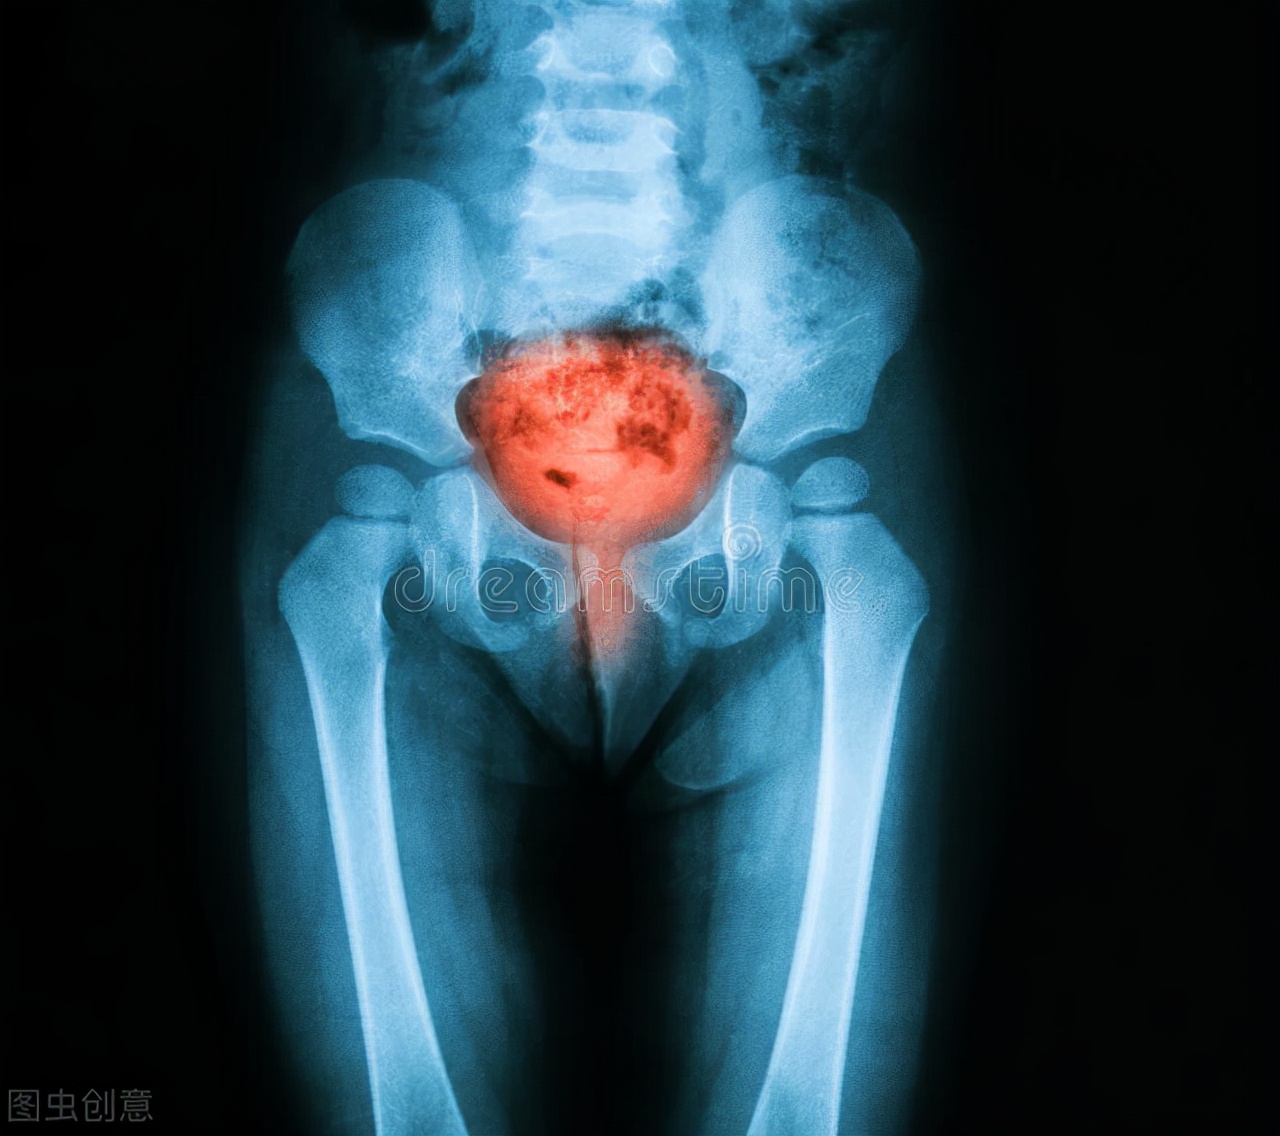

此时膀胱就像是一个注水的气球一般,身体依然每时每刻的生成尿液被带到膀胱,让我们的膀胱变得越来越充盈。为什么把膀胱比喻做气球呢?因为它像气球一样有延展性,但是不断地注水会让膀胱“气球”变得又大又薄,长时间处于这样的状态会让它失去延展性。“延展性”的理解就像一根橡皮筋,我们把它拉长放手它会马上回到原来的样子,但是我们一直把它拉长很长时间,它的延展性就会被破坏,放手的时候需要很长时间慢慢的缩回去,甚至不能完全缩回去。

由此来理解憋尿时间长尿得慢和无力,因为长时间憋尿膀胱“延展性”变差了,回缩的时间就变得很慢,而排尿的冲劲通常是由膀胱的弹性来决定,就像我们觉得尿急的时候马上去上厕所能够冲出很远。而且这也可以来解释老年人排尿无力的原因,随着年龄正常膀胱老化收缩能力大不如前了,所以就会排尿无力,而且膀胱收缩不彻底小便就排不干净,膀胱里总有一些排不完的小便,就总觉得想要长厕所。